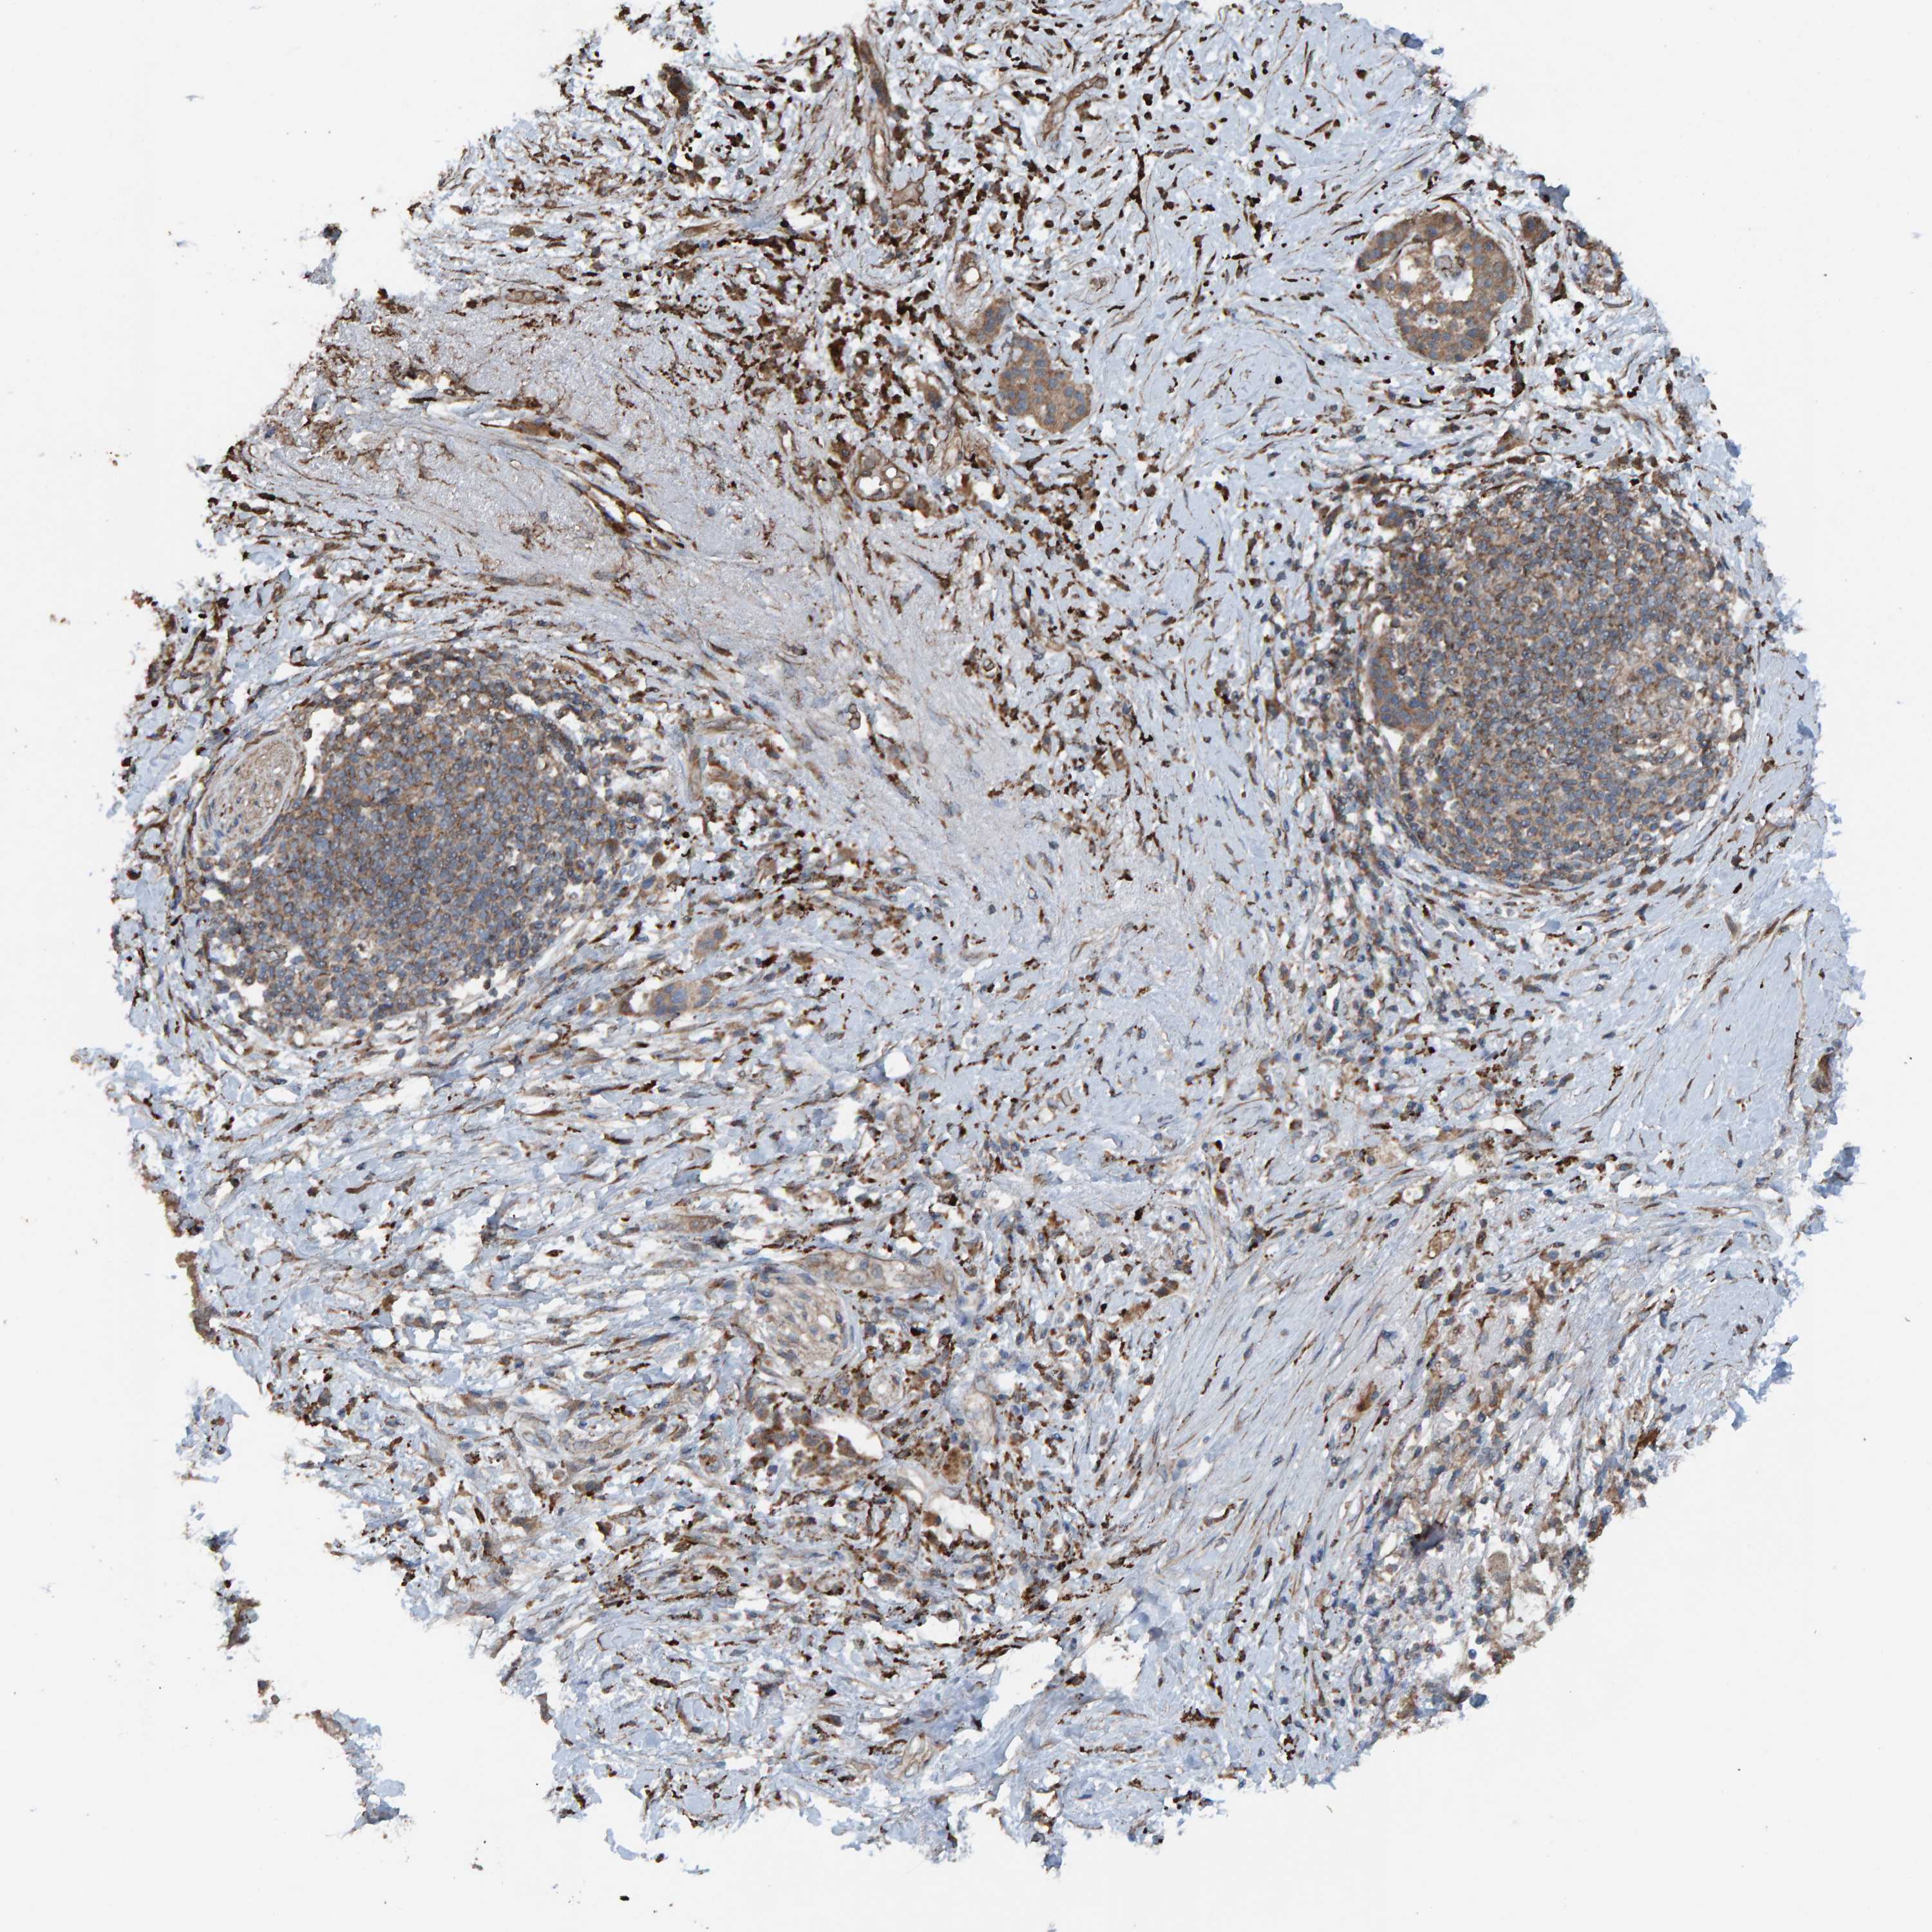

PANCREATIC CANCER - Protein expressioni

A mouse-over function shows sample information and annotation data. Click on an image to view it in a full screen mode. Samples can be filtered based on level of antibody staining by selecting one or several of the following categories: high, medium, low and not detected. The assay and annotation is described here.

Note that samples used for immunohistochemistry by the Human Protein Atlas do not correspond to samples in the TCGA dataset.

Antibody stainingi

Antibody staining in the annotated cell types in the current human tissue is reported as not detected, low, medium, or high, based on conventional immunohistochemistry profiling in selected tissues. This score is based on the combination of the staining intensity and fraction of stained cells.

Each image is clickable and will lead to virtual microscopy that enables deeper exploration of all samples and also displays staining intensity scores, fraction scores and subcellular localization as well as patient and tissue information for each sample.

Antibody HPA023384

Staining

High

Medium

Low

Not detected

Intensity

Strong

Moderate

Weak

Negative

Quantity

>75%

75%-25%

<25%

None

Location

Nuclear

Cytoplasmic/membranous

Cytoplasmic/membranous,nuclear

Adenocarcinoma, NOS